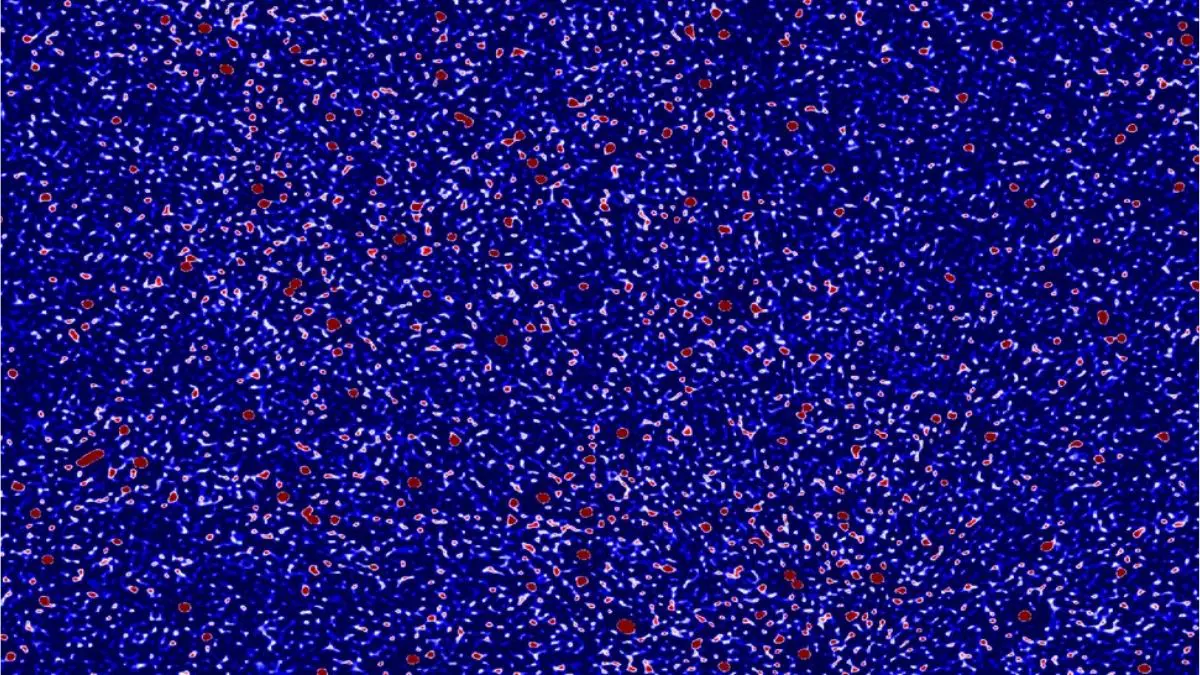

Novel Treatment Combination Improves Progression-Free Survival in Metastatic, Estrogen-Receptor-Positive HER-2-Negative Breast Cancer

Dr. Erica Mayer Patients with estrogen-receptor-positive HER-2-negative advanced breast cancer showed significantly improved progression-free survival when treated with an oral combination regimen that includes giredestrant, a novel, next-generation selective estrogen receptor degrader and full antagonist, compared to a standard combination approach. These findings, from the phase 3 evERA Breast Cancer study, are presented today by Dr. Erica Mayer of Dana-Farber Cancer Institute at the annual meeting of the European Society for Medical Oncology (ESMO) in Berlin, Germany.

Tumors that express the estrogen receptor (ER) account for roughly 70% of all breast cancer cases, and metastatic forms of these ER-positive cancers can be difficult to treat. In addition, the development of resistance to current endocrine therapies poses a major challenge for both clinicians and patients, underscoring the need for novel therapies that effectively target this breast cancer subtype.

“There is a significant need for therapies for metastatic ER-positive breast cancers that are more effective, particularly for patients whose tumors develop resistance to current endocrine therapies and who have progressed following treatment with CDK 4/6 inhibitors,” says Dr. Mayer. “In addition, we also need tolerable therapies that partner well with existing targeted agents and overall will improve outcomes for patients in the second line setting and beyond — when resistance is common and can be challenging to overcome.”

Giredestrant is a next-generation selective estrogen receptor degrader and full antagonist or SERD. It works by binding to the estrogen receptor and promoting its degradation, thus preventing estrogen from stimulating cancer growth. This new SERD has two important features compared to existing drugs. First, it has a unique mechanism of action relative to other hormone-blocking agents, which means it could benefit patients who develop resistance to current therapies. Second, giredestrant is administered orally, which is more convenient for patients than the monthly injections required for first-generation drugs.

evERA is a global phase 3, randomized, open-label study evaluating the use of giredestrant, in combination with everolimus, an mTOR targeting drug, in patients with ER-positive, HER-2-negative advanced breast cancer. This all-oral regimen is compared to a standard of care combination of endocrine therapy plus everolimus. evERA is the first positive, head-to-head phase 3 study of an all-oral SERD-containing regimen versus a standard of care combination.

A total of 373 patients were enrolled and randomized to receive either giredestrant plus everolimus or standard of care endocrine therapy and everolimus. About 55% of patients had mutations in the estrogen receptor gene (ESR1), indicating potential resistance to endocrine therapy. The study was designed to look for improvement in progression-free survival (PFS) using the giredestrant-based regimen in all patients (intention to treat, ITT) and in the subset of patients whose tumor had the ESR1 mutations.

With a median follow-up of 18.6 months, patients with tumors harboring an ESR1 mutation who received the giredestrant-containing regimen showed a statistically significant improvement in median PFS of 9.99 months, compared to 5.45 months for those who received the standard of care combination. That corresponds to a 63% reduction in the risk of disease progression or death.

In the ITT population, which includes patients with ESR1 mutations and those without, the patients who received the giredestrant combination showed a statistically significant improvement in median PFS of 8.77 months compared to 5.49 months for those treated with the standard of care combination. That corresponds to a 44% reduction in the risk of disease progression or death.

The overall survival data from the study remain immature but are trending favorably. In addition, the safety profile of the giredestrant regimen was manageable and consistent with the known safety profiles of the individual study treatments.

“Although we’ve made great progress in treating metastatic ER-positive, HER-2-negative breast cancer, these cancers can become resistant to existing therapies making them difficult to treat,” says Dr. Mayer. “The combination of giredestrant and everolimus is designed to address the most common resistance mechanisms. The evERA study is the first trial in this setting to show that using this new combination can substantially improve disease control compared to a standard of care combination regimen and may provide great benefit to a large number of patients with advanced breast cancer.”

Funding: The evERA Breast Cancer Study was funded by F. Hoffmann-La Roche Ltd.